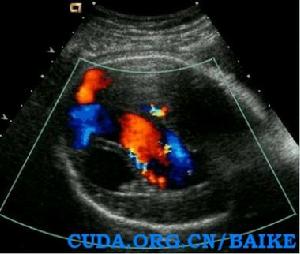

Galen靜脈血管瘤----由於動靜脈畸形導致Galen靜脈呈瘤樣擴張 ,但多在晚孕期(32孕周后)才能被檢出。

1)胎兒頭部在丘腦平面橫切時,近中線區、第三腦室後方、丘腦後下方探及一橢圓形無回聲囊性結構,囊壁薄而光滑,形態規則。